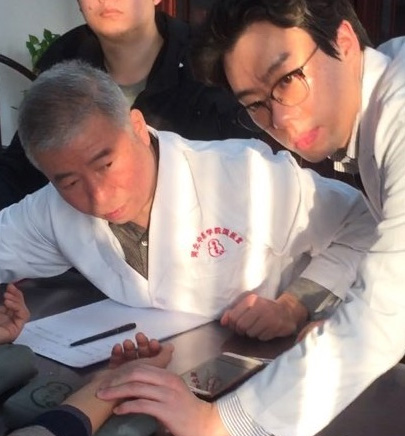

이사무 선생의 진료실에서

이사무 선생의 진료실에서